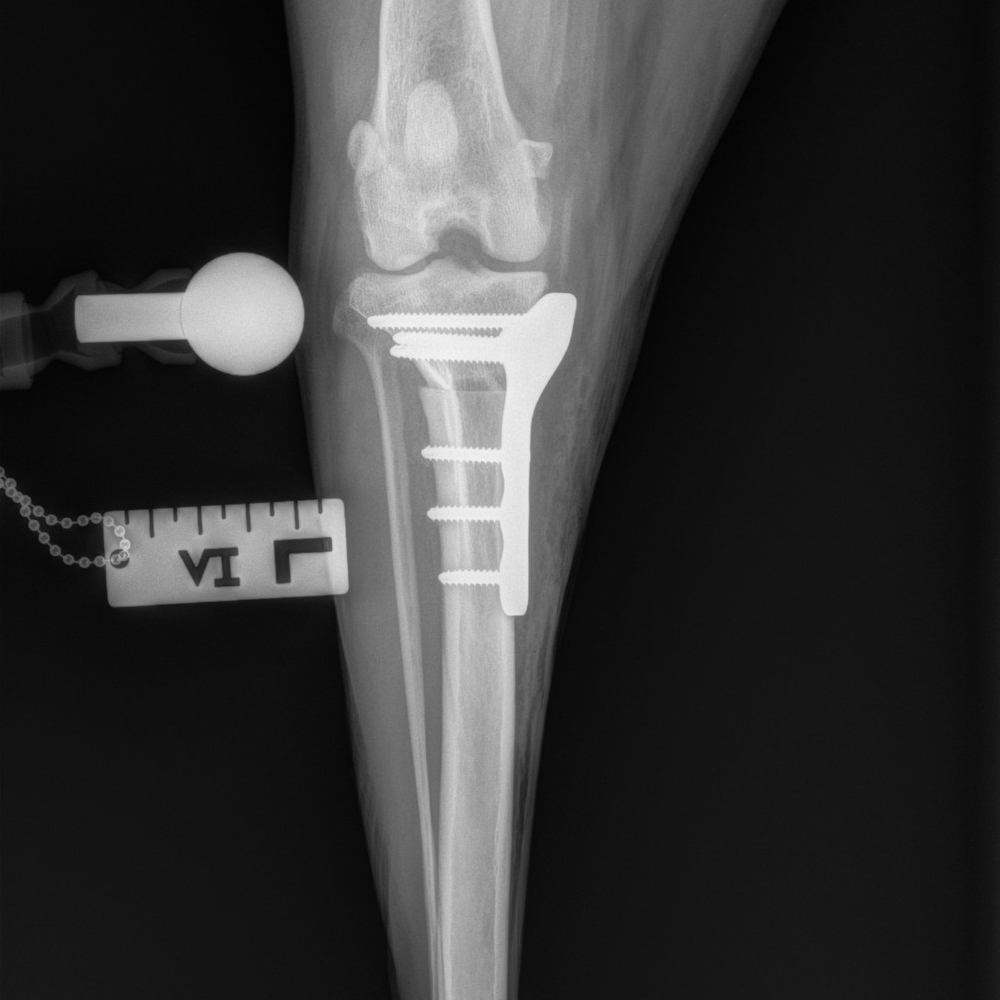

Tibial Plateau Leveling Osteotomy

This course is designed for veterinarians who want to specialize in orthopedic surgery and want to learn advanced techniques for managing knee injuries in small animals.